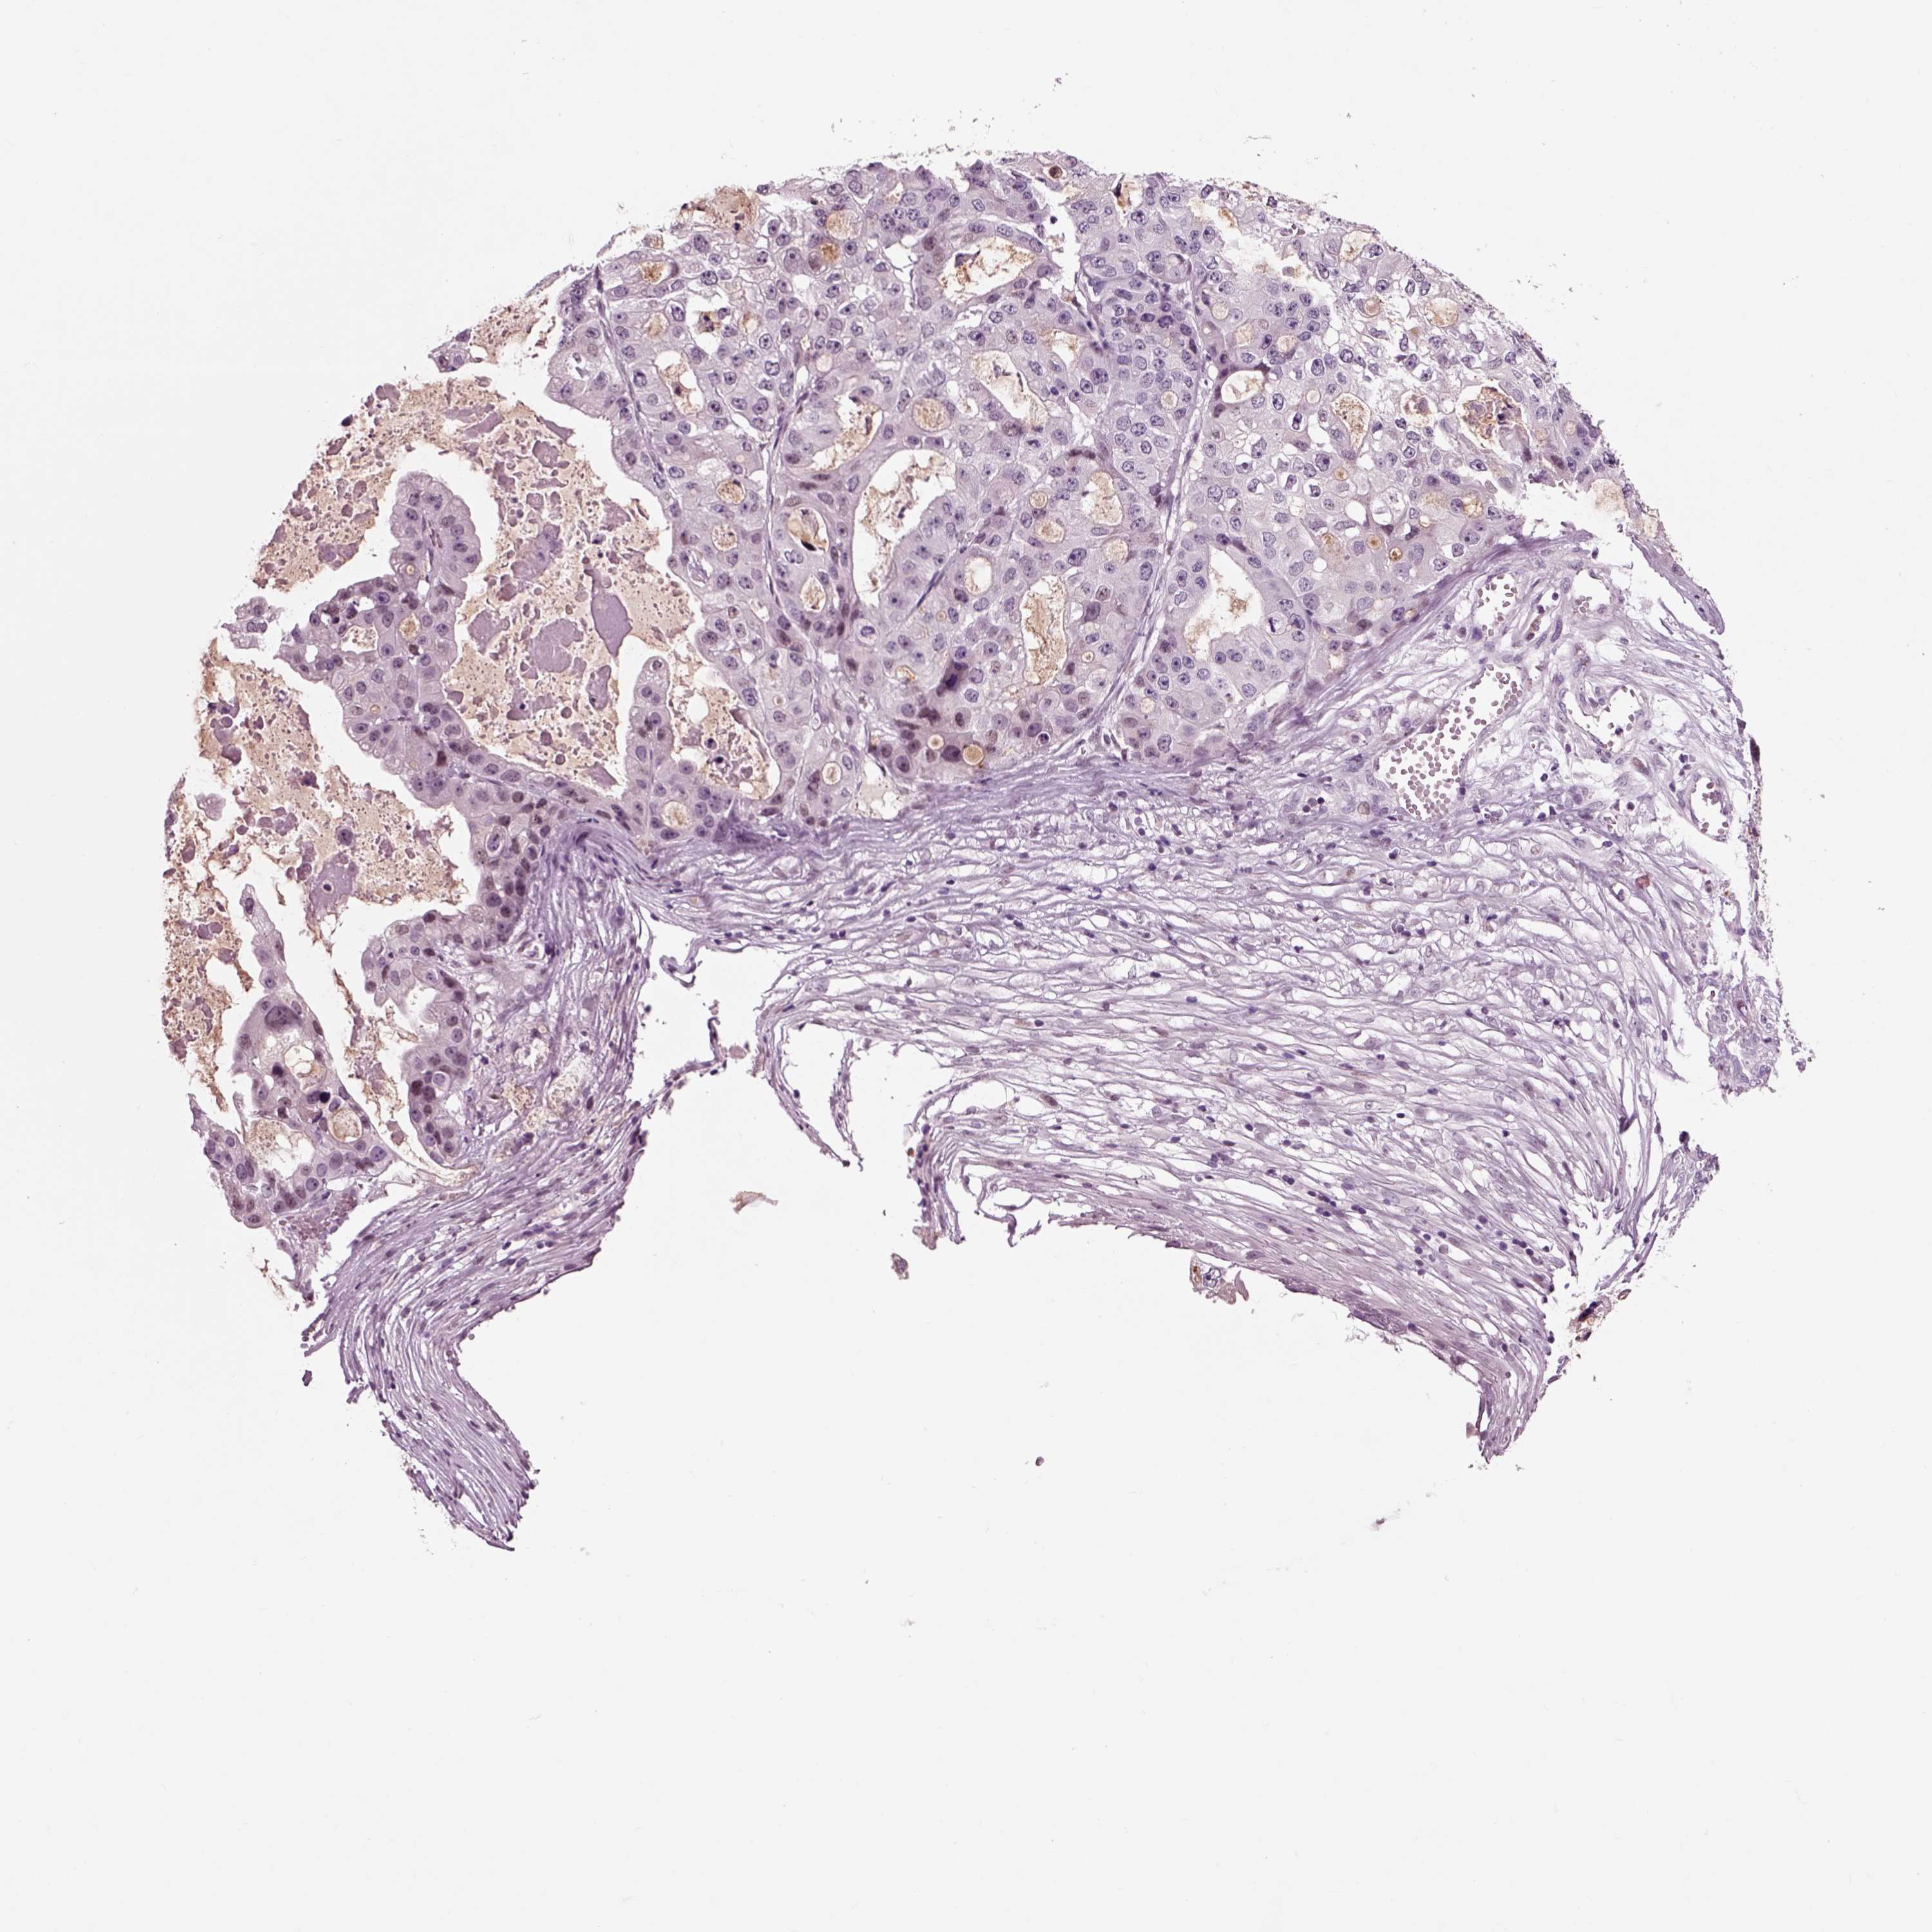

OVARIAN CANCER - Protein expressioni

A mouse-over function shows sample information and annotation data. Click on an image to view it in a full screen mode. Samples can be filtered based on level of antibody staining by selecting one or several of the following categories: high, medium, low and not detected. The assay and annotation is described here.

Note that samples used for immunohistochemistry by the Human Protein Atlas do not correspond to samples in the TCGA dataset.

Antibody stainingi

Antibody staining in the annotated cell types in the current human tissue is reported as not detected, low, medium, or high, based on conventional immunohistochemistry profiling in selected tissues. This score is based on the combination of the staining intensity and fraction of stained cells.

Each image is clickable and will lead to virtual microscopy that enables deeper exploration of all samples and also displays staining intensity scores, fraction scores and subcellular localization as well as patient and tissue information for each sample.

Antibody HPA012602

Cystadenocarcinoma, serous, NOS

Cystadenocarcinoma, mucinous, NOS

Carcinoma, endometroid